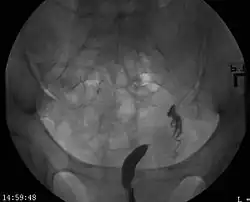

| A unicornuate uterus as seen on a hysterosalpingogram | |

Helpful techniques to investigate the uterine structure are transvaginal ultrasonography and sonohysterography, hysterosalpingography, MRI, and hysteroscopy. More recently 3-D ultrasonography has been advocated as an excellent non-invasive method to evaluate uterine malformations.[4]